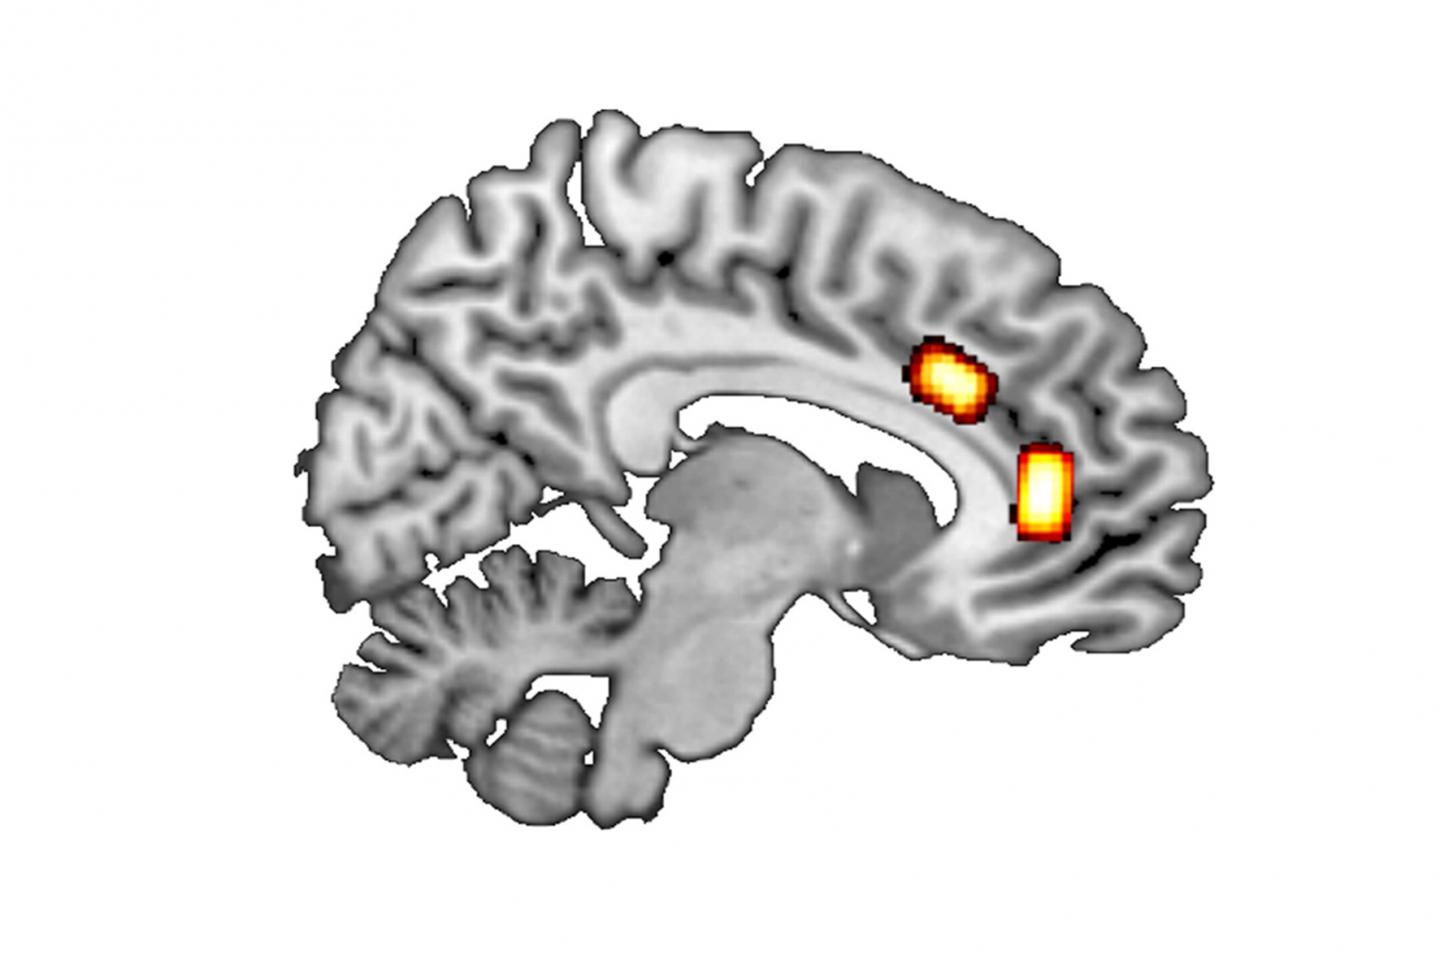

image: Longitudinal section of the brain: GABA/glutamate concentrations were measured at the locations marked (top: dorsal anterior cingulate cortex; further forward/bottom: ventromedial prefrontal cortex).

First, the researchers looked at so called ‘reward-based decisions’, which involve maximising reward by selecting the better of two options currently available. Luca Kaiser gives a simple example: “Where do I buy coffee on my way to work, depending on the price, quality and whether or not the café is on my way?” Previous results suggest that such decision-making processes in the brain are mainly processed in the ventromedial prefrontal cortex (vmPFC).

Unlike these reward-based decisions, ‘patch-leaving decisions’ are about long-term strategic considerations that include a careful balancing of immediate cost against (long-term) gain. An example of such a decision would be whether to move from Düsseldorf to Munich for a job offer. Prof. Jocham explains: “The job in Munich may offer a higher salary and a more interesting role, but may also involve stress and the effort involved in finding a place to live and moving to Munich – as well as higher rents and the loss of social contacts in Düsseldorf.” Thus, there are many factors that influence this type of decision. According to the literature, such decisions are made in the brain’s dorsal anterior cingulate cortex (dACC).

The two messenger substances glutamate and GABA may play a key role. The ratio between them, the so-called E/I balance, indexes the balance between excitatory and inhibitory neural transmission. The researchers used magnetic resonance spectroscopy to measure the concentrations of GABA and glutamate in different cortical areas of human volunteers.